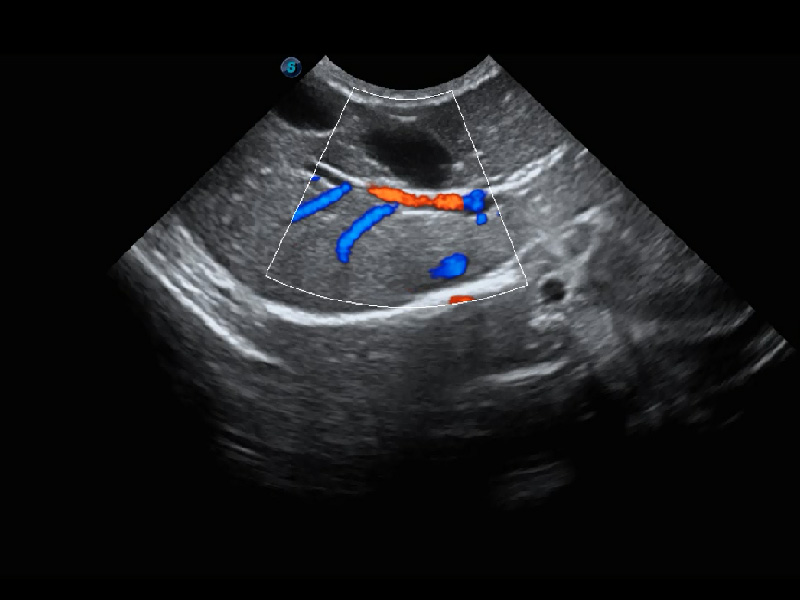

ProPet 60 作为一款高端台式动物超声设备,为动物医生的日常诊断提供了一系列贴合动物临床需求、解决临床实际问题的高级成像功能。凭借全系列高清探头,满足医生对腹部、心脏、生殖、浅表、肌骨等成像的所有需求,切实帮助您提升检查效率,提高诊断信心。

动物是人类最亲密的朋友和最值得信赖的伙伴。环球UG官网也一直致力于探索动物专用的超声影像解决方案。 全新推出的ProPet系列,是环球UG官网在动物超声影像智能化、专业化、精准化的一次跨越式革新。动物不能用言语来表述自己的不适,通过超声影像,ProPet系列搭建了动物医生与不同物种沟通的“桥梁”,为动物医生注入了“治愈之力”。